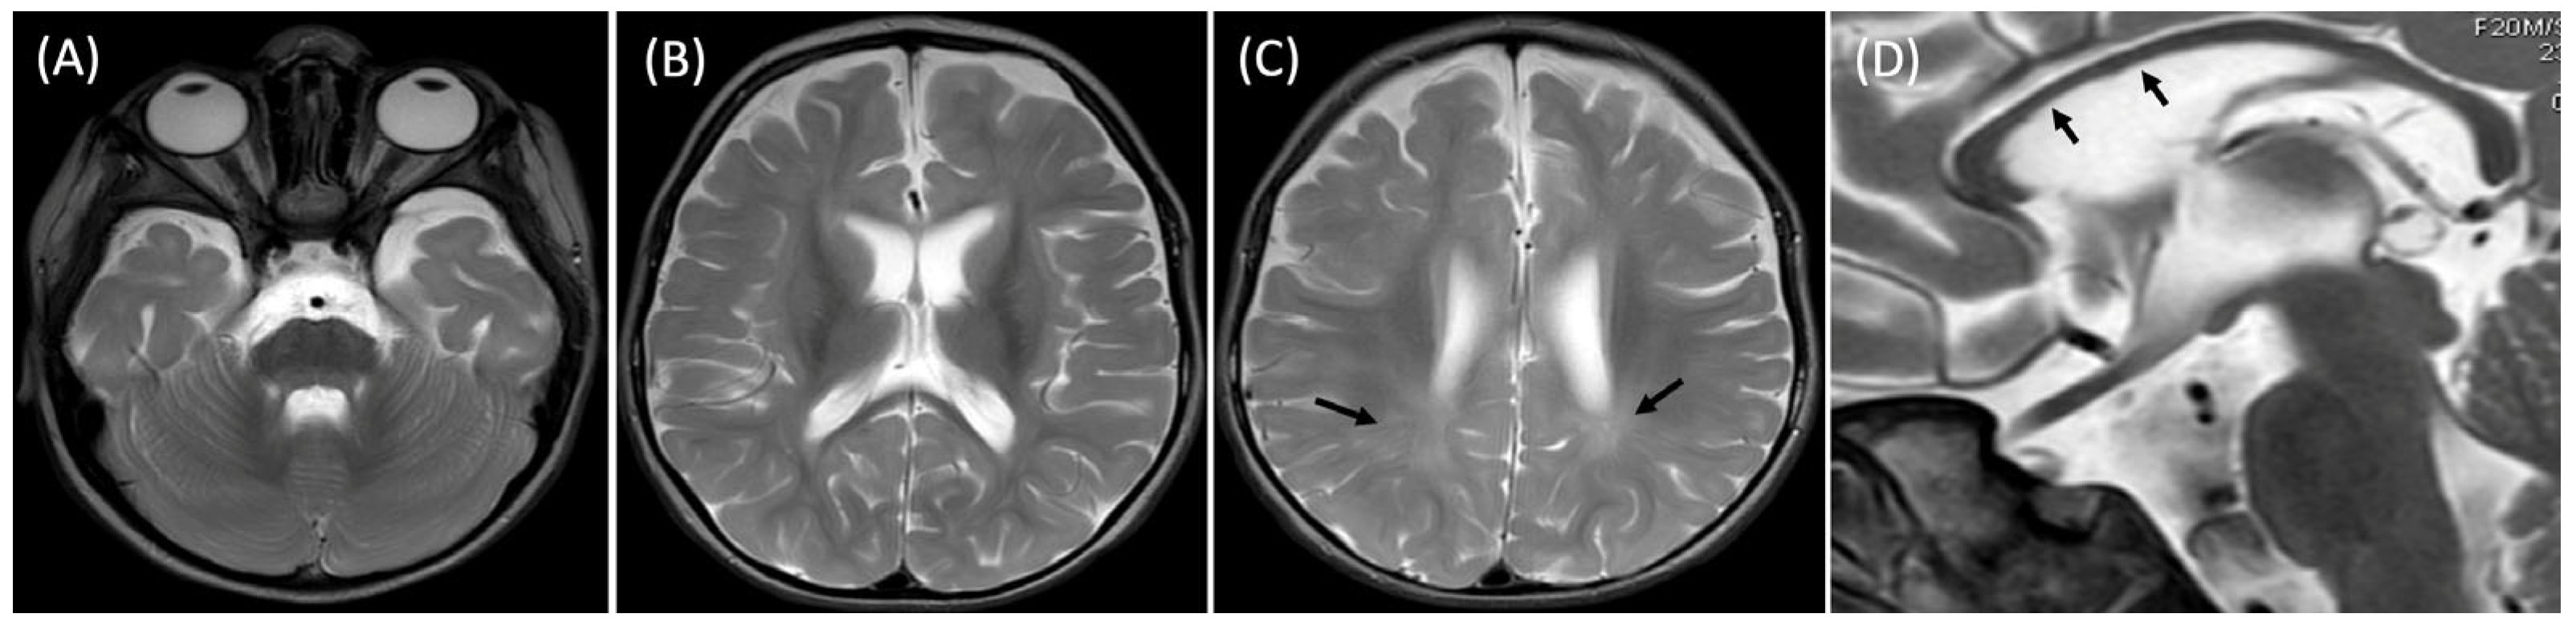

At 20 months, the brain MRI revealed mild generalized atrophy of the cortex and the white matter, bilateral T2 hyperintensities of the posterior portions of the white matter indicating its delayed myelination and slightly hypoplastic corpus callosum (Figure 3).

Neuroimaging findings in our patient, including cortical atrophy, delayed myelination, and a hypoplastic corpus callosum, are consistent with previously reported MRI patterns [1]. These structural abnormalities reflect the central role of SPATA5L1 in neuronal maintenance. Biochemical studies indicate that SPATA5L1 protein, together with SPATA5, forms the heterohexameric AAA+ ATPase complex (55LCC), which safeguards replisome proteostasis and ensures genome integrity [2].

Figure 3. Axial T2-weighted brain MR images (AC) showing anterior temporal hypoplasia (A) and widened pericerebral fluid spaces (B,C) indicating cortical volume loss as well as mild ventriculomegaly (B,C) consistent with white matter atrophy and periventricular T2-hyperintensities (C, arrows) suggestive of delayed white matter myelination. Sagittal T2 weighted image (D) showing thin corpus callosum (arrows).